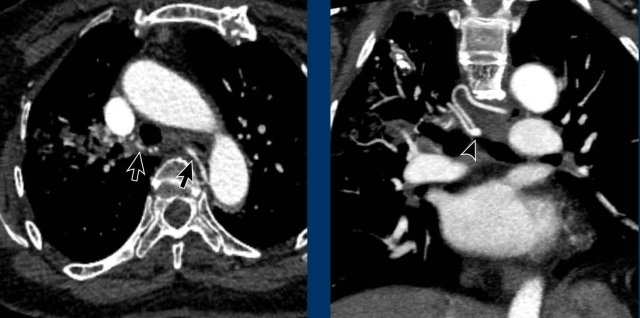

Image

Central wall-adhering thrombus in a patient with chronic thrombo-embolic disease with right heart dilation, consistent with chronic thrombo-embolic pulmonary hypertension (CTEPH).